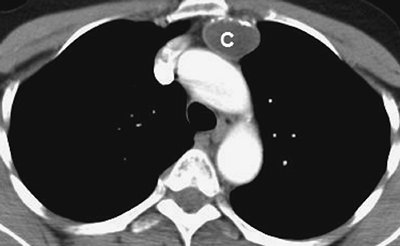

FIGURE 6-32. Esophageal duplication cyst. CT scan of a 45-year-old woman shows a subcarinal cystic structure (C) of homogeneous fluid attenuation in contact with the esophagus (arrow). The appearance is indistinguishable from that of a bronchogenic cyst.